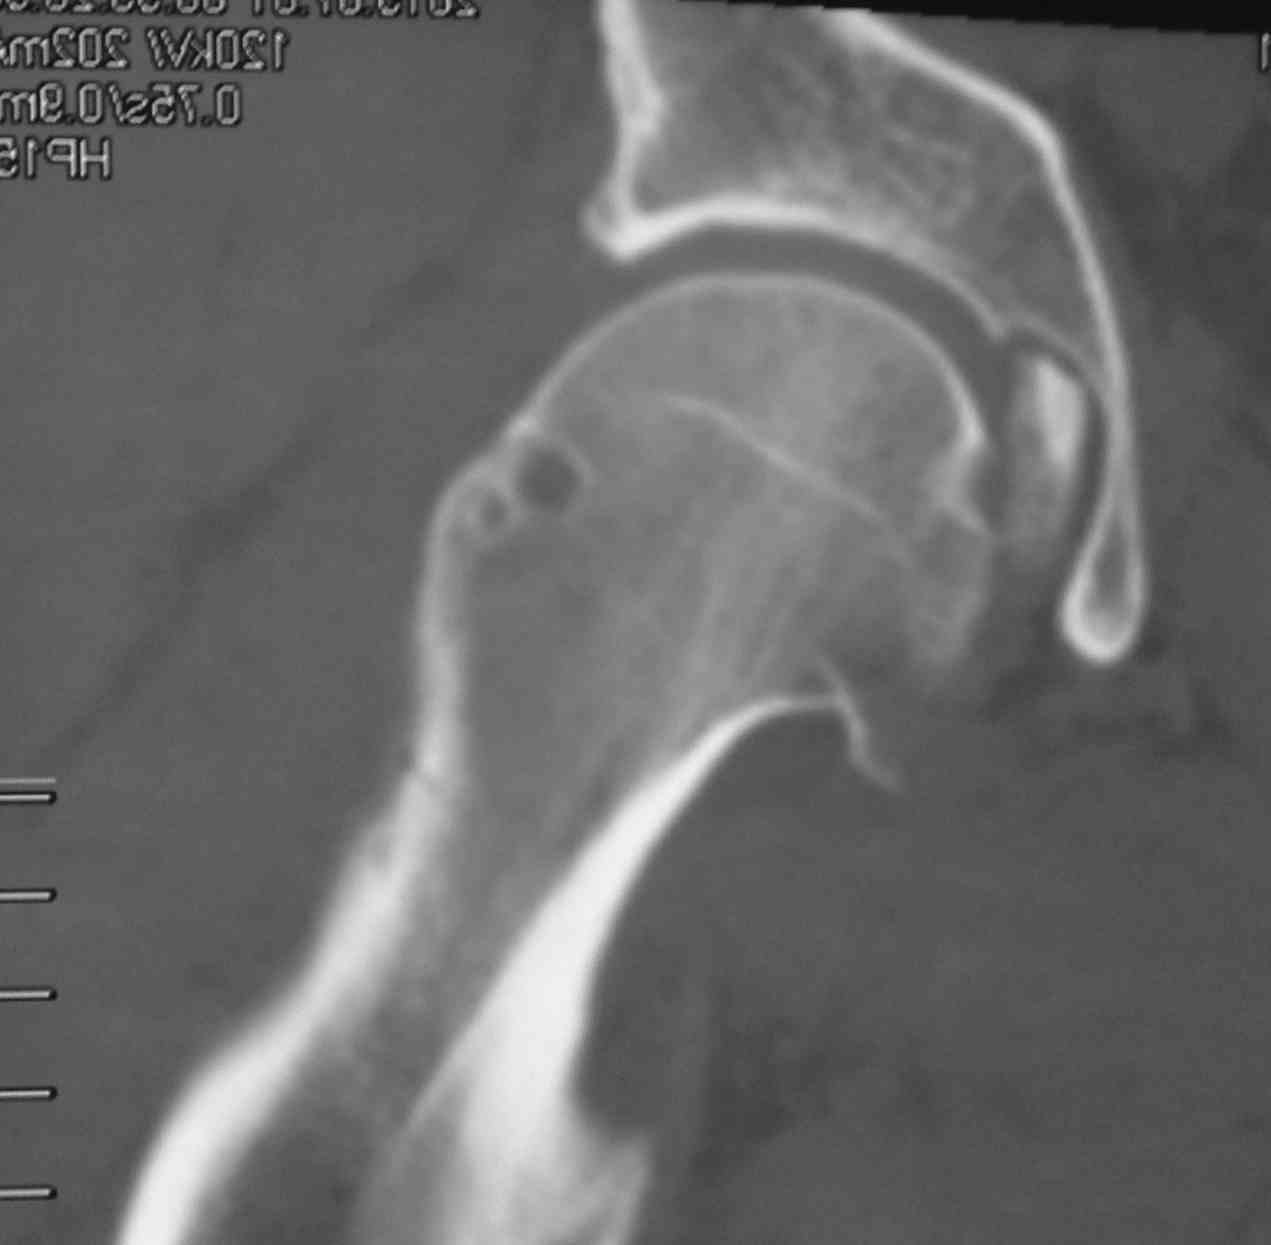

[Ortho] перелом проксимальной тибии + вывих бедра

скан, который, на мой взгляд наиболее интересен